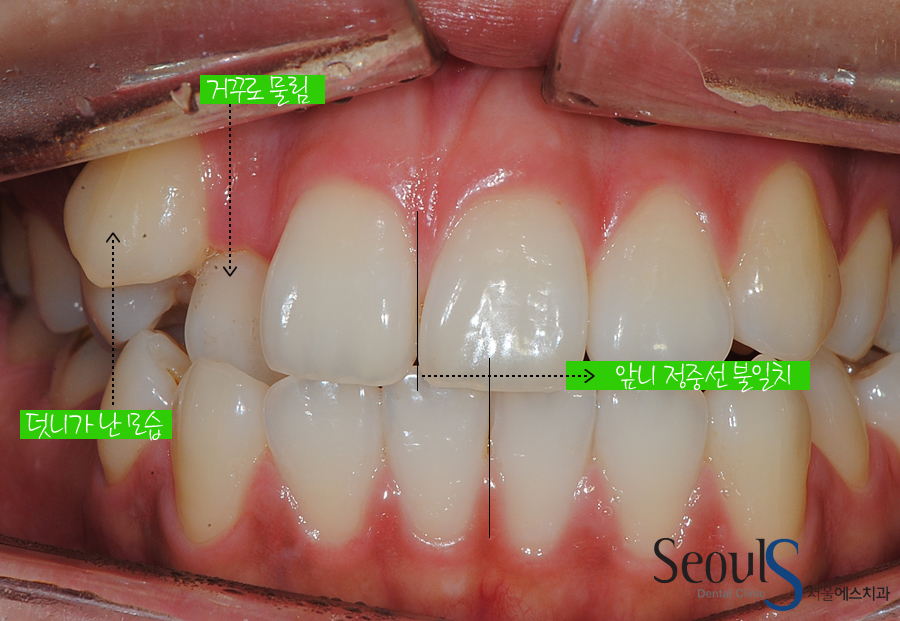

{덧니 발치교정}

보시는 사진은 배열이 어긋난 치아를 치아교정을 통해 바로잡아준 모습입니다

보시는 치아는 위턱과 아래턱~

즉, 골격적인 부분은 정상이나

공간 부족으로 인한 치아배열 이상(덧니)과 위아래 중심선이 맞지 않는 비대칭 문제를

가지고 있었습니다

또한 위, 아래의 끝이 물리는 부정교합의 문제도 관찰되었습니다.